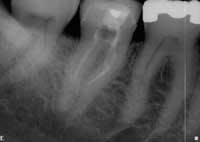

This is rarely satisfactory to the patient and/or doctor and not a profitable method of practice. We all know, or should know, our degree of skill, equipment, and comfort level. As clinicians, few of us can be all things to all people. If we know of a clinician who is more skilled in a given endodontic area, we are duty-bound to act in the best interest of the patient and refer. As a practicing endodontist, I refer a limited number of patients for IV sedation, as required. The patients who get the best possible treatment, even if referred elsewhere, can become our greatest advocates because they know we have their best interest at heart. The converse is true. The “I’ll try anything” mentality can bring forth iatrogenic events that rarely leave the tooth with the same integrity that it would otherwise have. Work that has to be re-treated is never profitable (see Figs. 1 and 2).